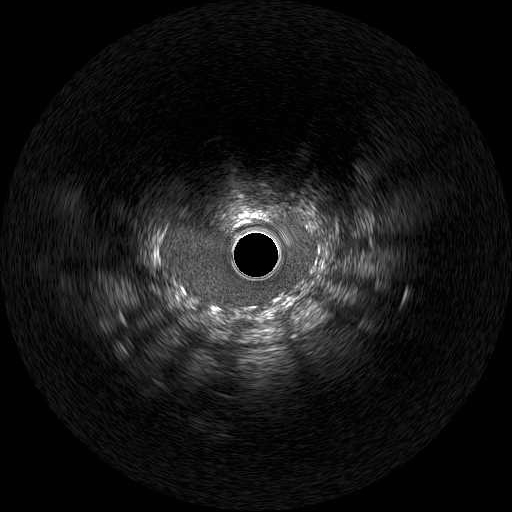

We used 7Fr JR3.5SH guiding and SION blue ES wire. Wire was easily crossed, and IVUS showed in-stent restenosis with neointimal hyperplasia and underexpanded stent. Long inflation technique using cutting balloon was performed, and Biolimus-A9 coated stent was deployed for in-stent lesion. Post dilation using NC balloon was performed, and procedure was completed. 4 months and 1year and 9 months after the procedure, follow up CAG with coronary angioscopy was performed.

1 year and 2 months after the initial procedure using underexpanded stent for eccentric calcified plaque placed at RCA ostium, in-stent restenosis was occurred. PCI was performed with drug-coated balloon and another 8 months later, re-restenosis was occurred. PCI was performed again with Biolimus-A9 coated stent deployed for in-stent lesion. 4 months, and 1 year and 9 months after the stent implantation, CAG was performed with evaluating coronary angioscopy. At the 4 months later, there was no restenosis and we confirmed beginning of neointima coverage for stent strut. At the 1 year and 9 months later, there was also no restenosis, and we confirmed enough and optimal neointimal coverage as vessel healing after stent implantation. Biolimus-A9 coated stent has early drug release system and polymer-free characteristics. The characteristics of the stent may have contributed to get the early smooth and optimal neointimal coverage, and the prevention of malignant cycle of RCA ostium in-stent restenosis.